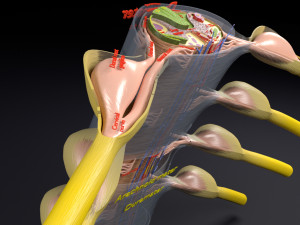

spinal fixation system - titanium bracket. human spine, spinal cord, sacrum and fixation system medically accurate high quality 3d model.

hi-poly 3d model of human spine with internal structure.

더 보기hi-poly 3d model of human spine with internal structure.

spine fixation spinal cord screw surgery system anatomy backbone bone brace bracer bracket column disc paralyze titanium treatment vertebra이 아이템에 대한 코멘트 없음.